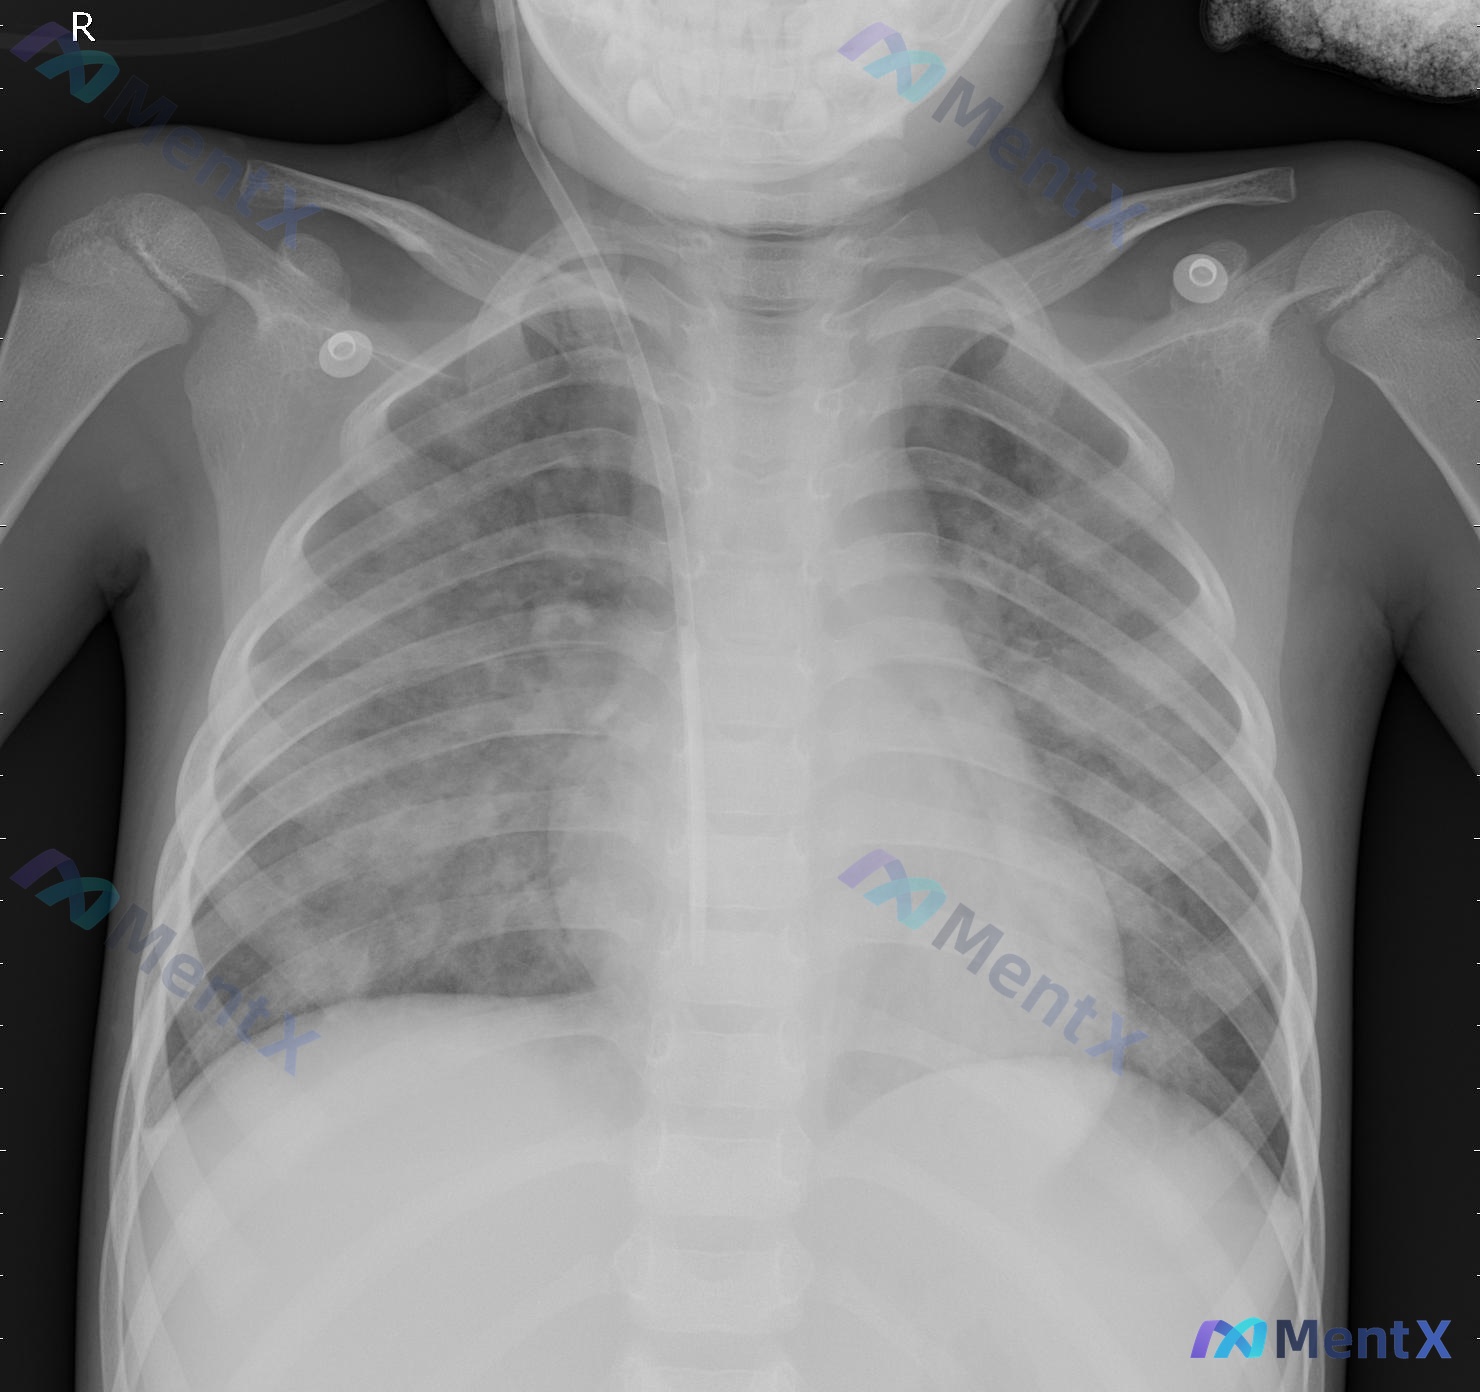

这个婴幼儿胸部X光片,第一眼只想到肺炎,第二个要排除什么高危情况?

整理了一份婴幼儿前后位(AP位)胸部X光片的影像资料,先不说结论,只看描述和分析里的几个点,想请大家先讨论一下: 基础背景:从胸廓和胸腺影(右上纵隔帆征)看,是婴幼儿。 影像核心表现: 1. 双肺纹理增多、增粗、紊乱,双肺门影增大、模糊; 2. 双肺中内带及肺门旁可见散在斑片状、云絮状密度增高影;...